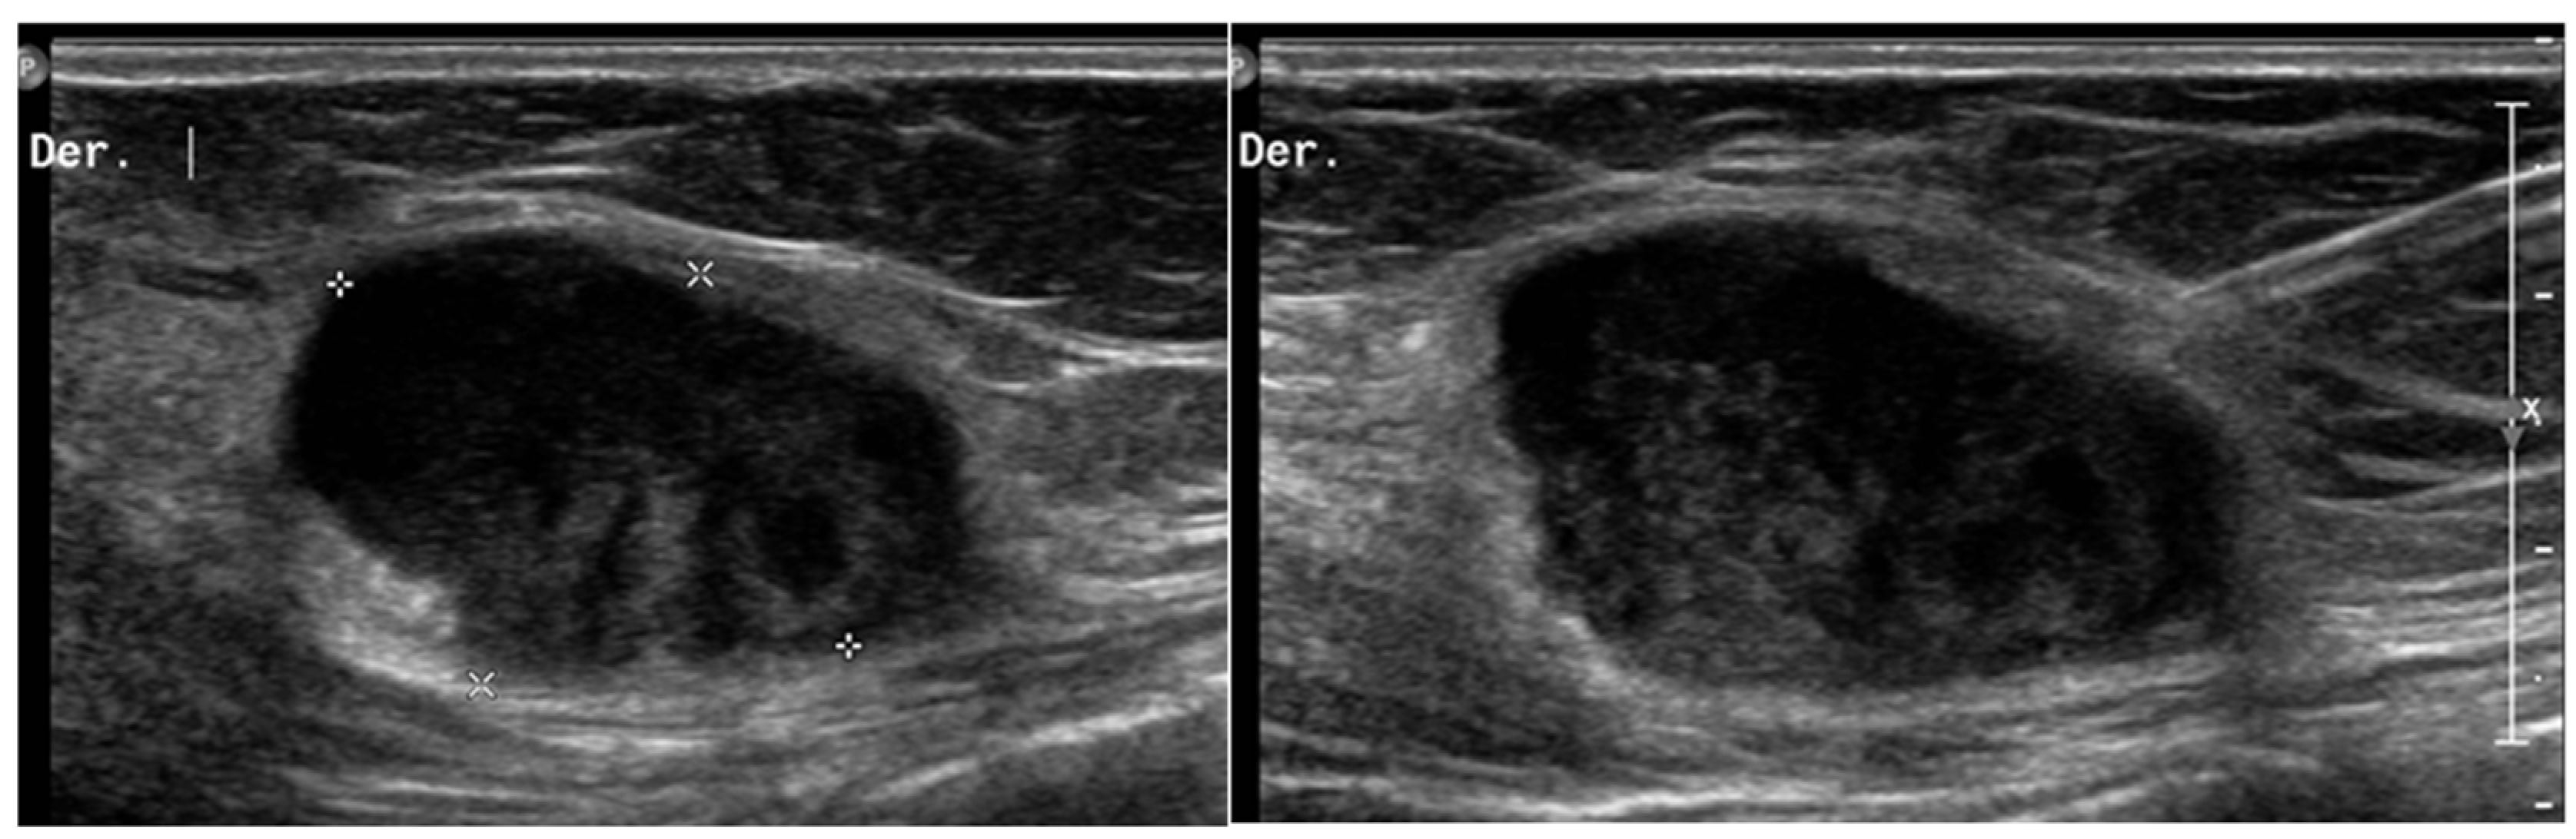

- Gastrointestinal Stromal Tumors (GIST): either primary (extraintestinal GIST, “EGIST”) [25,26] or secondary GIST of the abdominal wall are rare. When extended (>5 cm), GIST may have an aggressive behavior [25]. CT is the imaging modality of choice, showing heterogeneous vivid enhancement, and variable amount of necrosis. Peculiar findings include calcifications and cystic degeneration [27,28,29].